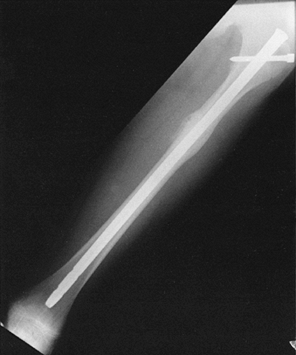

adolescents, standard intramedullary fixation with interlocking may be

can be safely applied to children (Fig. 164.8).

as the Ender nail (See Chapter 19 and Chapter 20).

In stable fractures, flexible intramedullary nails can be inserted

|  |

| Figure 164.8. Interlocked intramedullary nail used to fix femoral-shaft fractures in children with open physes. |